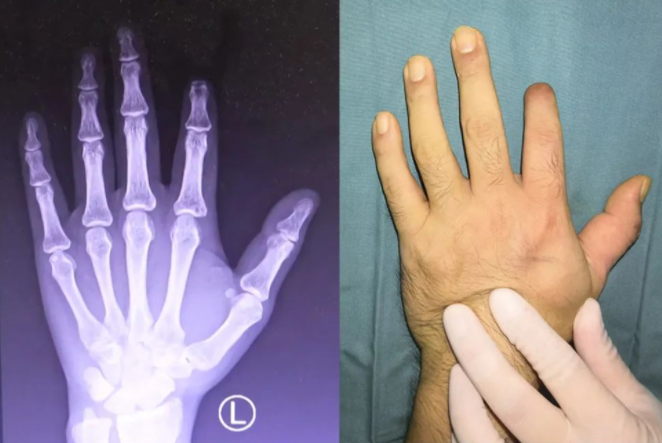

2个月前,远在新疆工作的小高扣篮时,左手手指不慎被篮筐刮住,鲜血瞬间涌出,示指第一指节处皮肉离断,白骨外露。小高立即前往当地医院进行示指再植手术,可惜并未成功。术后虽好转出院,但缺损的示指成了小李的心头病。

10月上旬,小高与妻子通过互联网医院进行了预约挂号。赶到医院后,在手外科门诊如期见到方杰医生。通过仔细的查体后,方杰医生给了焦虑的小高一颗“定心丸”,通过“移花接木”,能让手指重新“长”出来。

入院第二天,手外科郑大伟主任、方杰医生为小高进行了“左手示指全形再造术”。术后,小高左示指血运正常,再造成功。